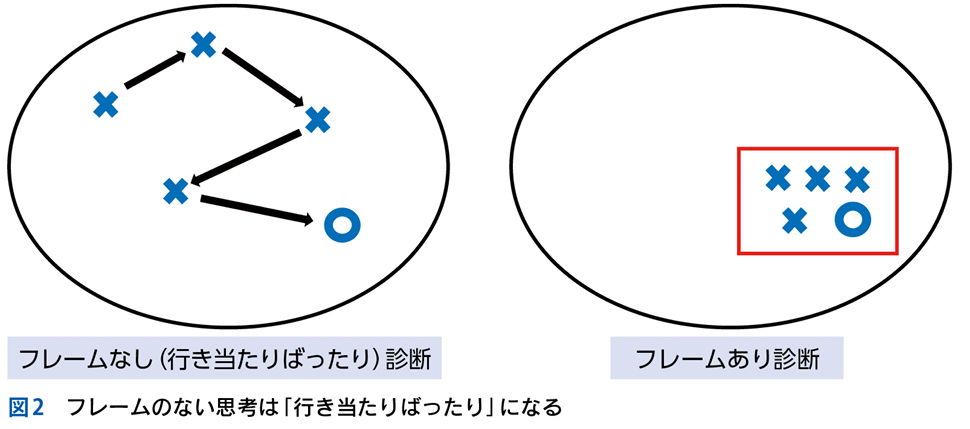

▶ 分析的診断推論とは,論理的に選び出した,可能性のある複数の診断を検討することである。膨大な数の疾患の中から可能性のある診断群を選び出すためには,まず疾患全体を含む空間の中に,「この内側に確実に真の診断がある(この外側には確実に真の診断はない)」という「枠」を置くことが必要である。仮にそうせずに推論を進めるのであれば,広大な空間内から行き当たりばったりで疾患を選んでいくことになる。これは要するに直観的診断の繰り返しであり,システム1が磨かれていなければ当たるも八卦,当たらぬも八卦で診断にたどり着けるかどうかわからない。

▶ また,「行き当たりばったり」アプローチを採った場合には鑑別診断のリストは生成されないため,「可能性があるが否定できていない疾患」が何なのかを知ることはできない。したがって「可能性のある他の疾患を除外する」ことで診断されるタイプの疾患(多くの膠原病など)の診断は本質的に困難となるし,後述する「診断が明確でないときに,安全な場所に自分を置く」(悪いアウトカムをもたらす鑑別を除外しつつ時間を使う)という戦術も利用することができない。

▶ 疾患全体という空間内に診断の可能性を限定する「枠」(フレーム)を置くことは,分析的診断の必要条件となる重要な一歩である(図2)。これを筆者は「フレーミング」と呼ぶ。